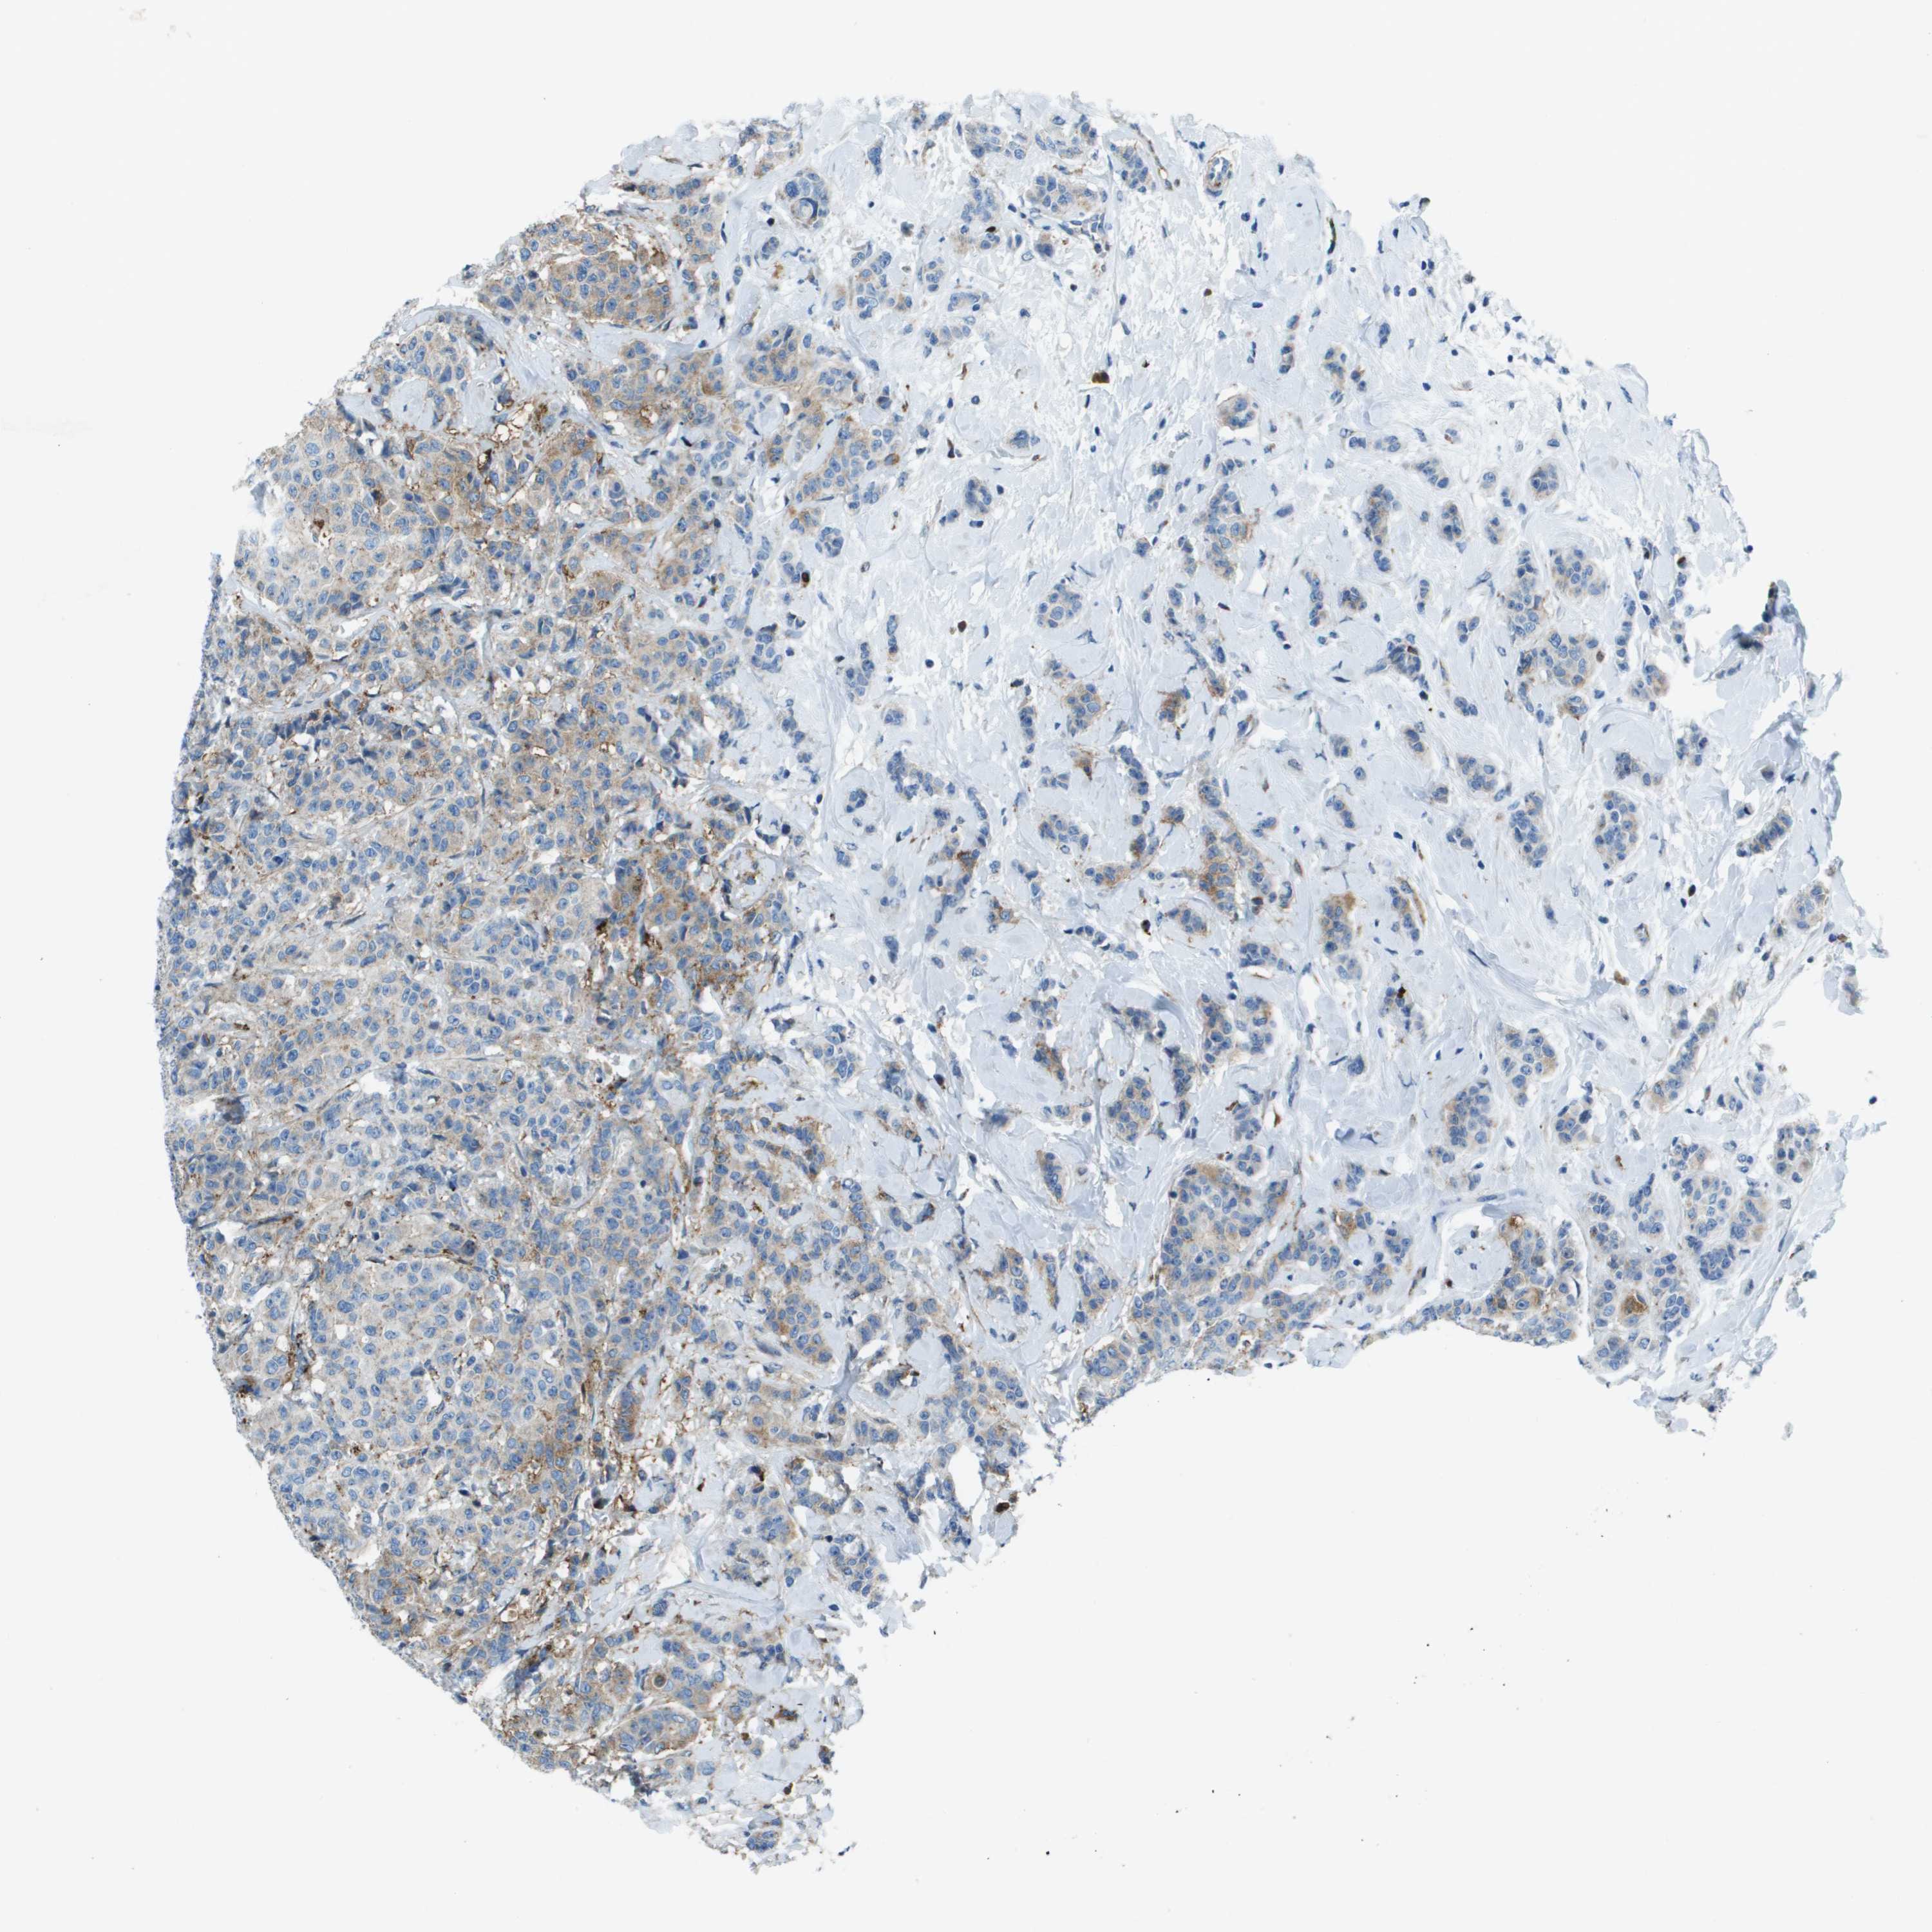

BRCA TCGA BRCA VALIDATION PROTEIN EXPRESSION

ANTIBODIES

AND

VALIDATION

SDC1 is potential prognostic, high expression is unfavorable in Breast Invasive Carcinoma (TCGA)